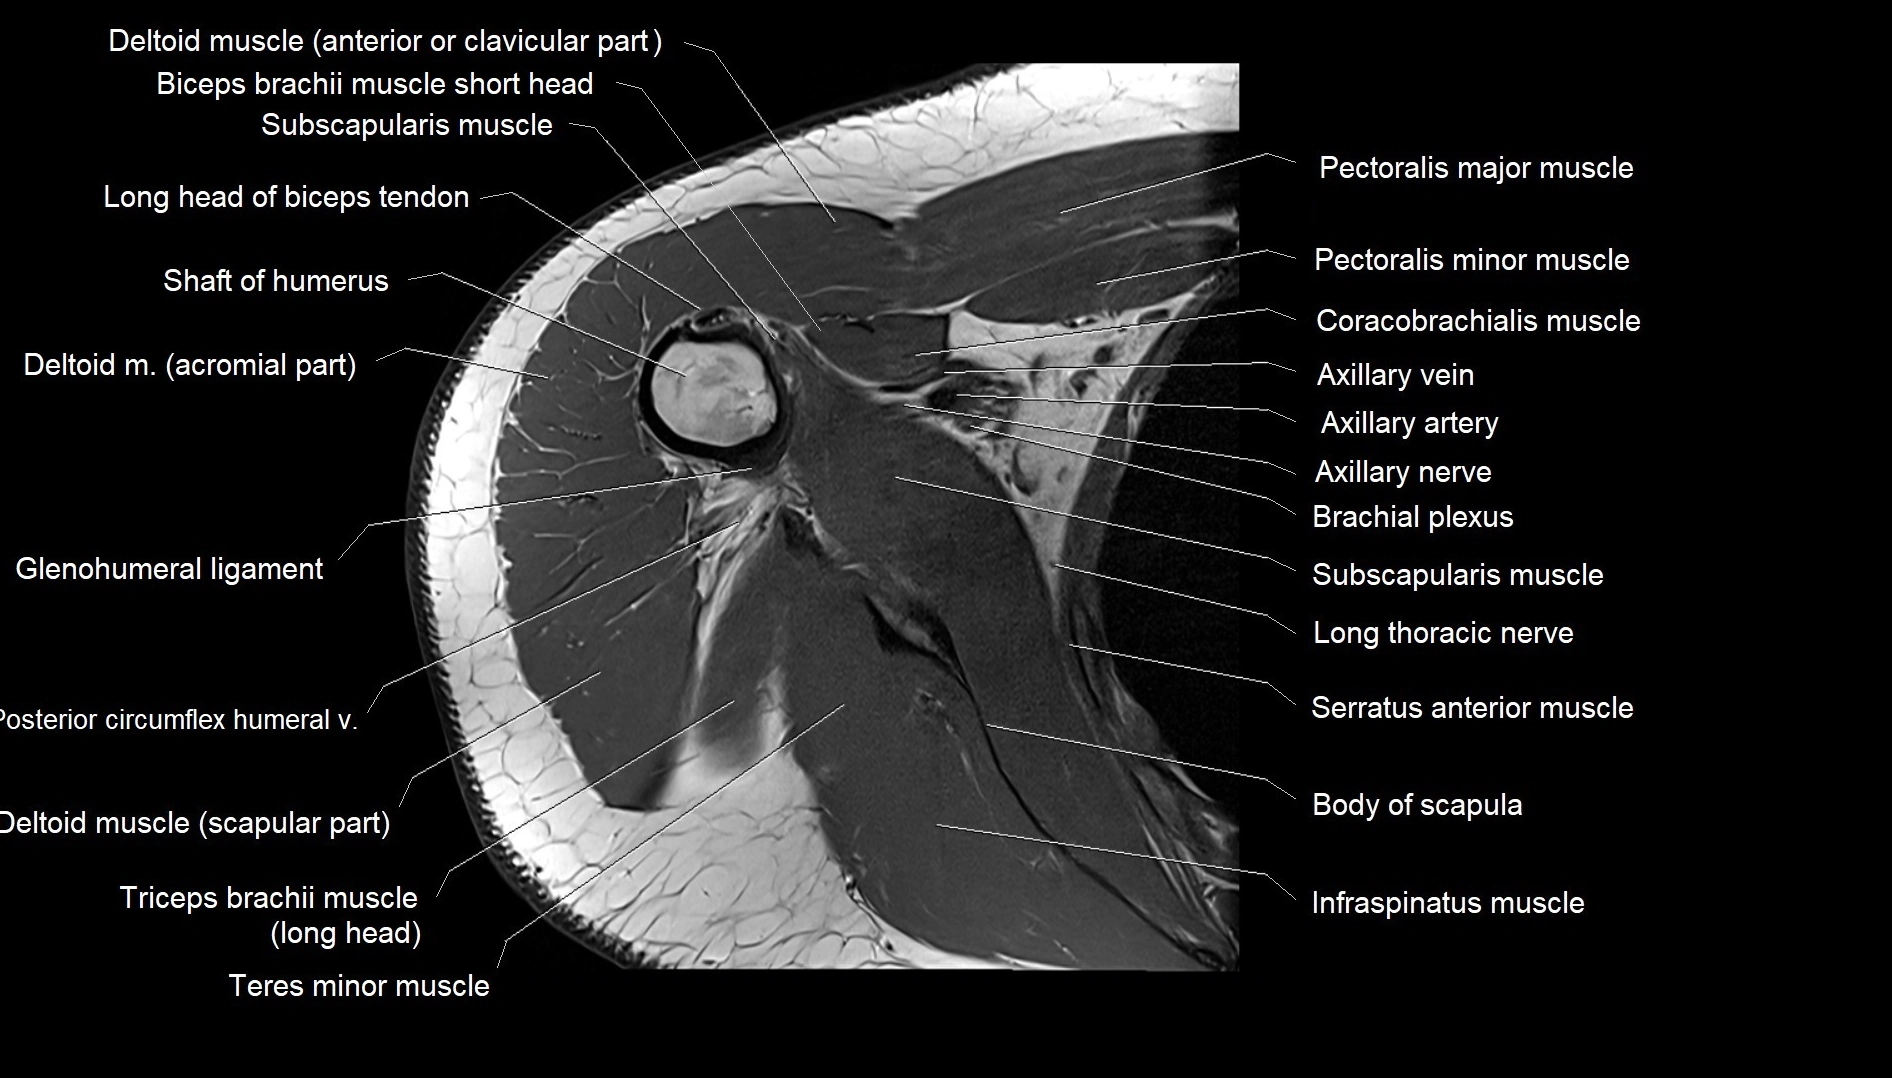

MRI images

image